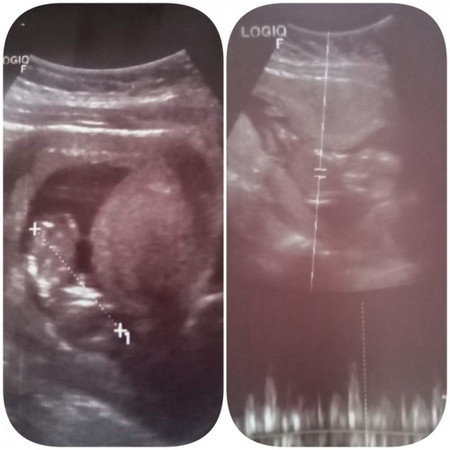

อยากถามแม่ๆว่าแตกต่างกันมั้ยคะรูปที่1ตอน12วีค3วันรูปที่2ตอน15วีค4วัน

บ้านนี้เพิ่งไปซาวมาวันนี้ตอน15วีค4วันแต่ในใบซาวเขียน13วีค6วันขนาดน้องแค่7.8เซน แบบนี้น้องไม่โตรึวัดค่าน้องผิดคะเจอหมอแต่ละครั้งคนละคนทุกรอบ 2รอบแรกหมอวัดตรงพอรอบนี้ยังงงทำไมห่างกันเยอะจัง